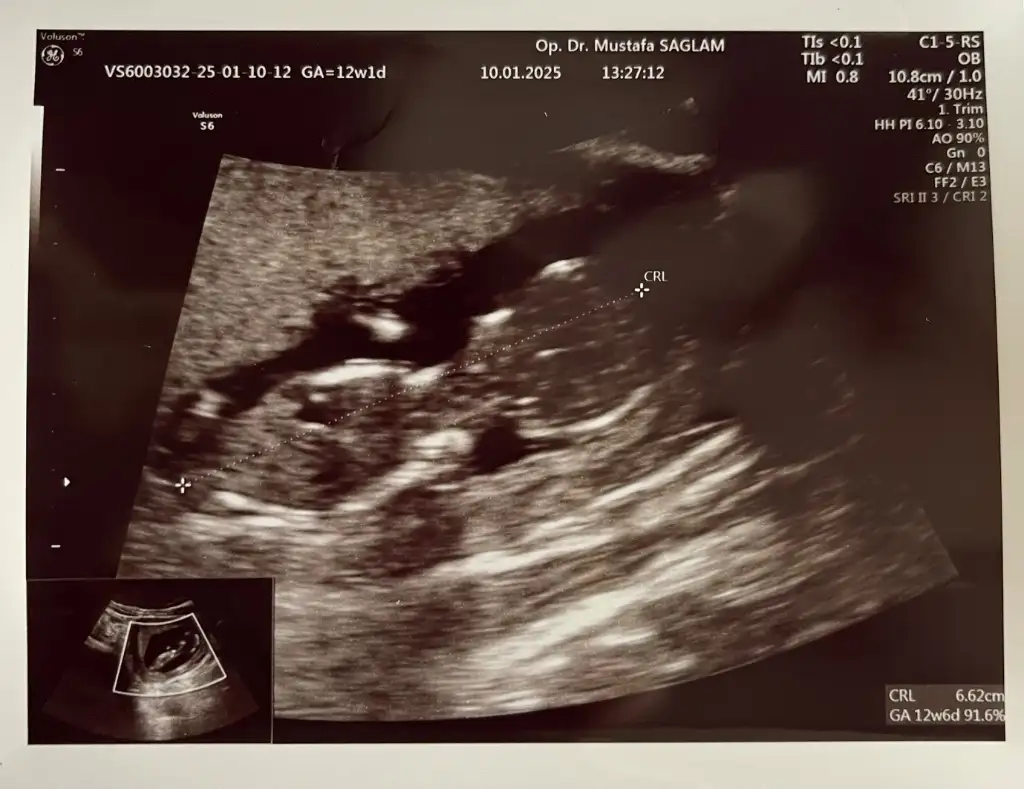

Buda 12+2 hala aynı fikirde misiniz acaba?

• IMG_7083.webp

IMG_7083.webp

39,9 KB · Görüntüleme: 40